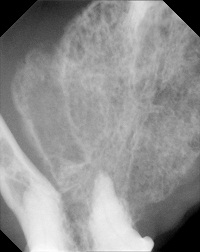

Om een goed beeld van de tumor te krijgen is vaak sedatie nodig. Tijdens deze sedatie kan de uitgebreidheid van de tumor bepaald worden. Tevens kunnen dan, indien nodig, ook röntgenfoto’s van de kaak genomen worden en kunnen histologische biopten genomen worden om de diagnose te bevestigen. De regionale lymfeklieren kunnen nagevoeld worden en aangeprikt worden. Vergroting van de mandibulaire lymfeknopen kan veroorzaakt worden door metastasen, maar zal vaker secundair aan de in de tumor aanwezige ontsteking zijn. Zoals eerder vermeld worden metastasen op afstand, zoals in de longen, zeer zelden aangetroffen omdat de patiënten meestal niet lang genoeg leven om deze te ontwikkelen. Dit maakt het nemen van thoraxfoto’s in het kader van stageren dubieus. In die gevallen, waar een zeer uitgebreide tumor aanwezig is, kan men het nemen van thoraxfoto’s overwegen, maar moet men zich realiseren dat de uitkomst hiervan de therapie zeer waarschijnlijk niet zal beïnvloeden.

Bij orale plaveiselcelcarcinomen kunnen op röntgenfoto’s soms uitgebreide benige veranderingen zichtbaar zijn. Links is de röntgenfoto van de kat van de bovenste afbeeldingen in de inleiding.